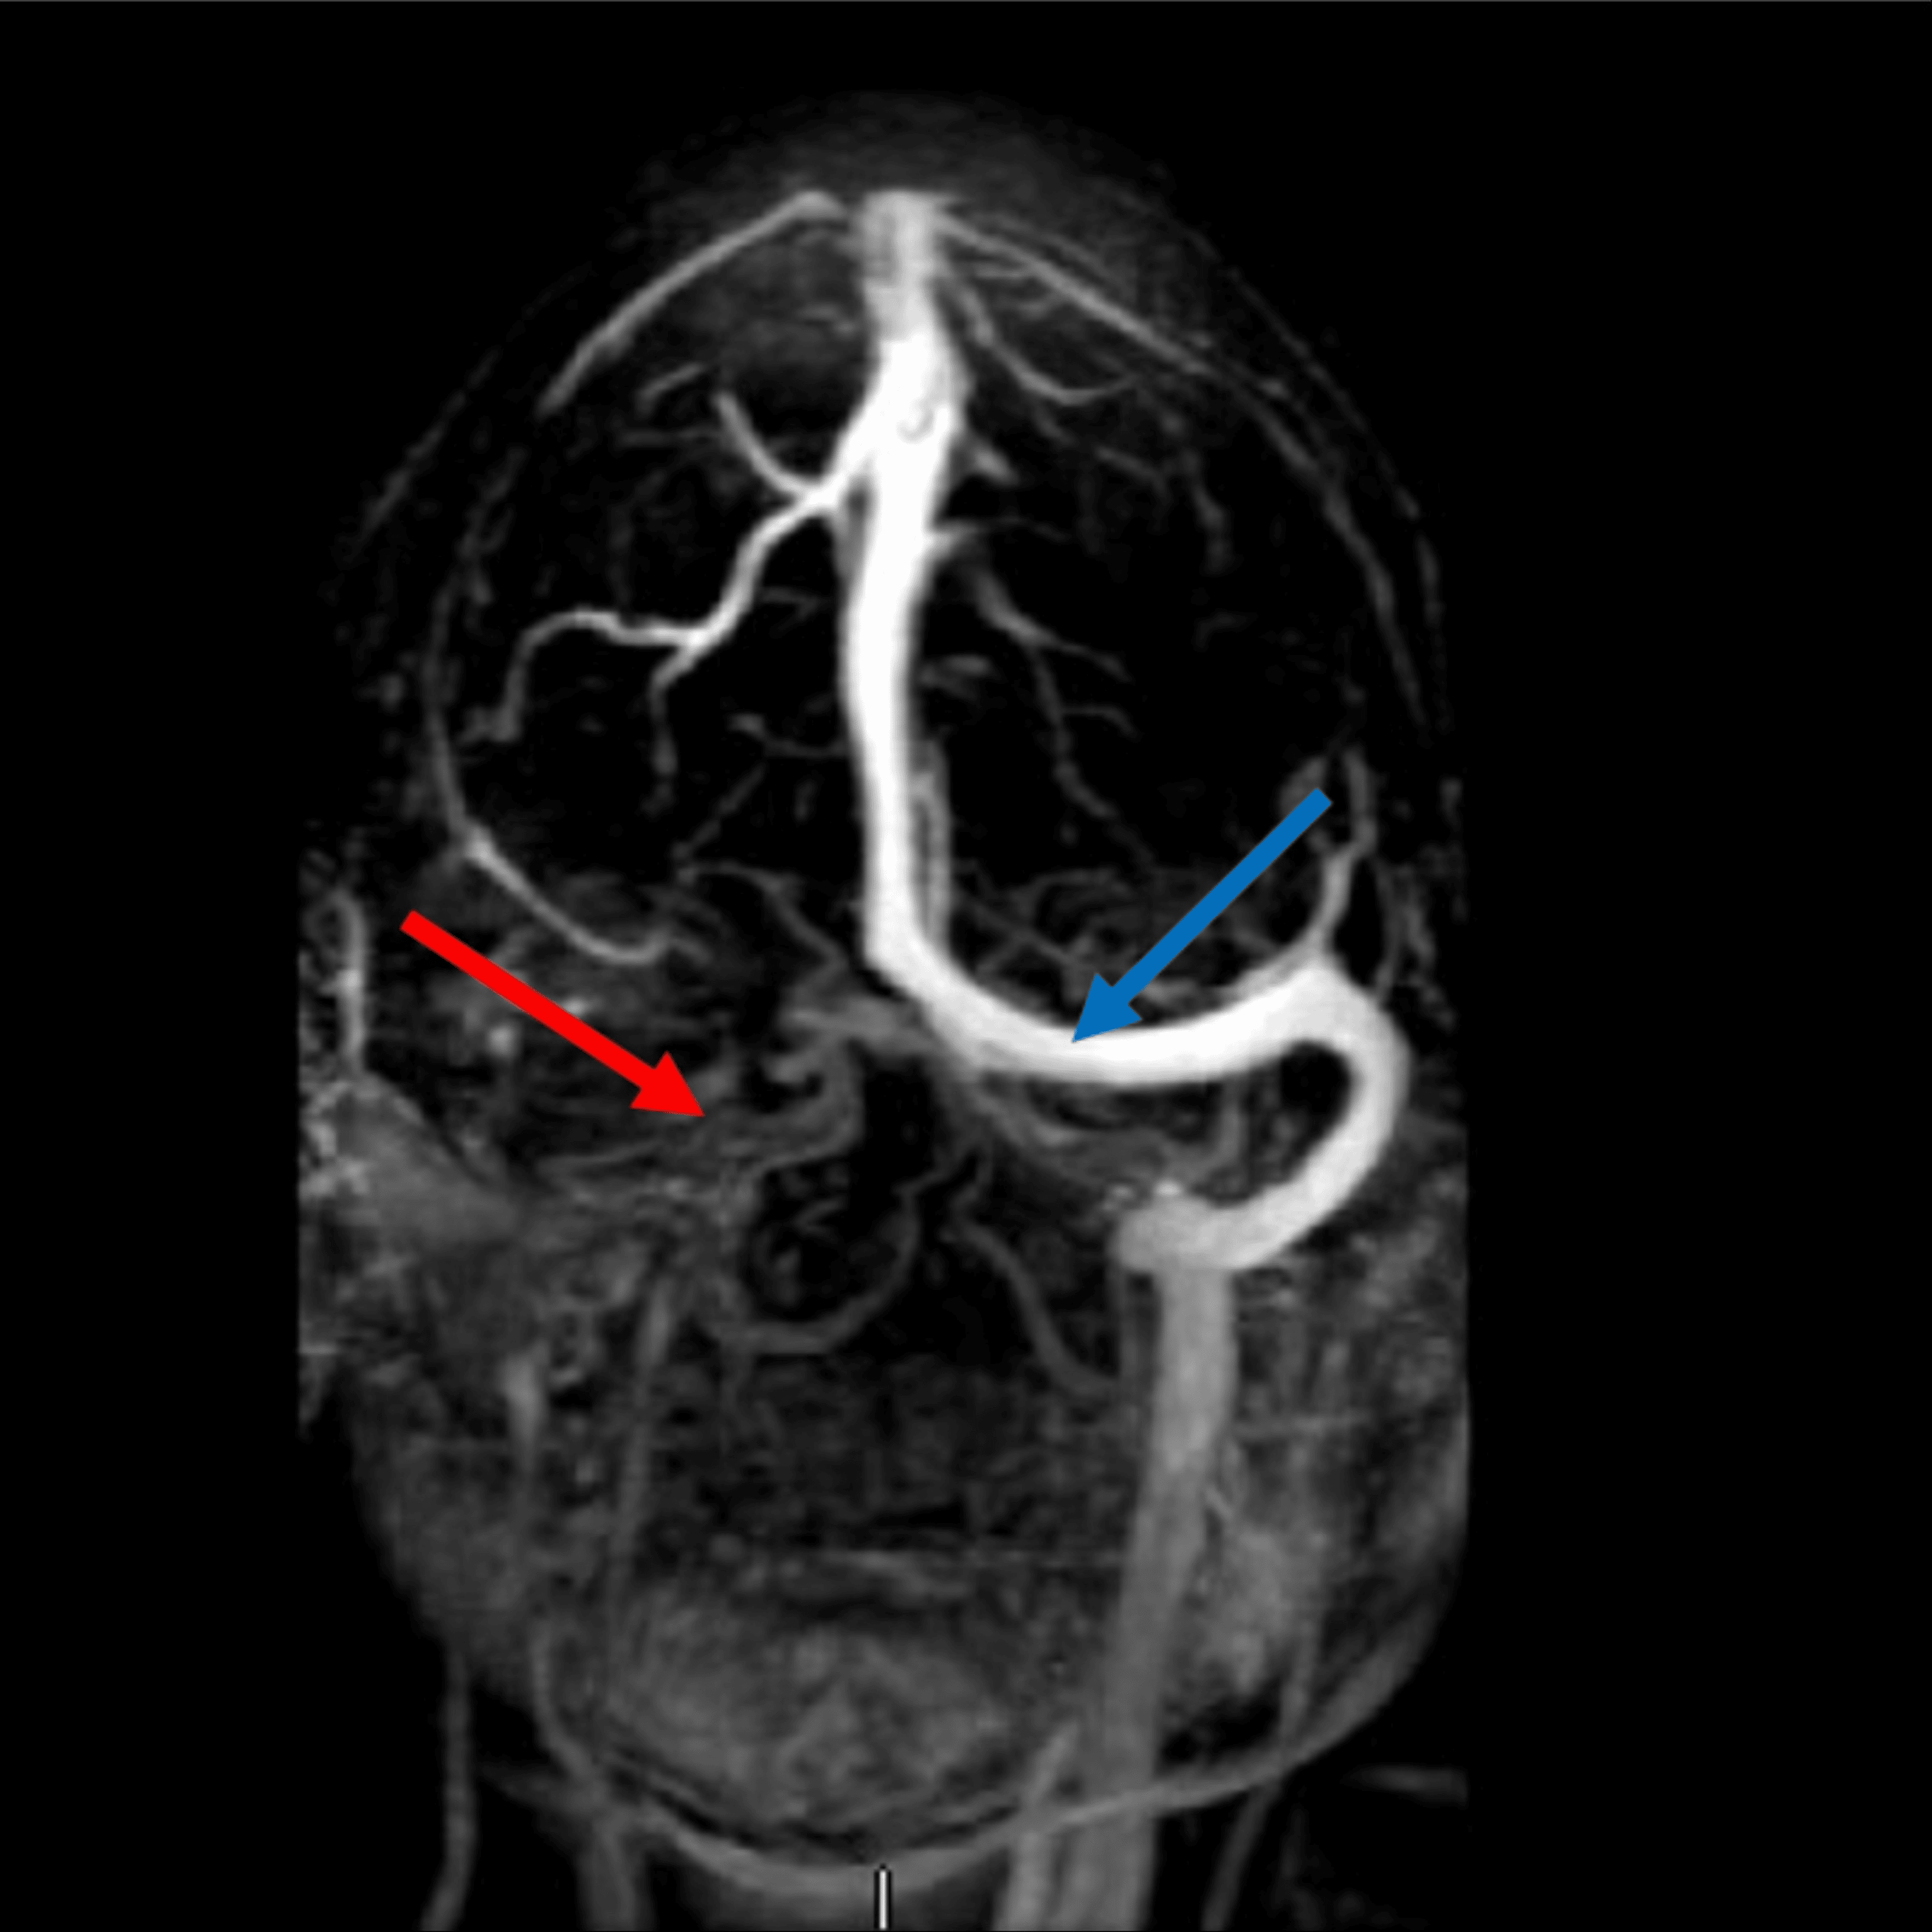

From www.cureus.com

Hereditary Protein S Deficiency and Activated Protein C Resistance Protein S Deficiency And Epidural For women with a family history of vte who have protein c or protein s deficiency, the ash guideline panel suggests postpartum. Protein s deficiency is an inherited thrombophilia associated with an increased risk of thromboembolism. A deficiency in protein s characteristically demonstrates the inability to control coagulation, resulting in the excessive. Recently, gris and colleagues reported that treatment with. Protein S Deficiency And Epidural.

Hereditary Protein S Deficiency and Activated Protein C Resistance Protein S Deficiency And Epidural For women with a family history of vte who have protein c or protein s deficiency, the ash guideline panel suggests postpartum. A deficiency in protein s characteristically demonstrates the inability to control coagulation, resulting in the excessive. Recently, gris and colleagues reported that treatment with 40 mg enoxaparin daily in pregnant women with a thrombophilia. In summary, the successful. Protein S Deficiency And Epidural.

From www.semanticscholar.org

Figure 1 from Hereditary Protein S Deficiency and Activated Protein C Protein S Deficiency And Epidural In summary, the successful anesthetic management of a patient with protein s deficiency and ischemic heart disease is described. Recently, gris and colleagues reported that treatment with 40 mg enoxaparin daily in pregnant women with a thrombophilia. A deficiency in protein s characteristically demonstrates the inability to control coagulation, resulting in the excessive. For women with a family history of. Protein S Deficiency And Epidural.